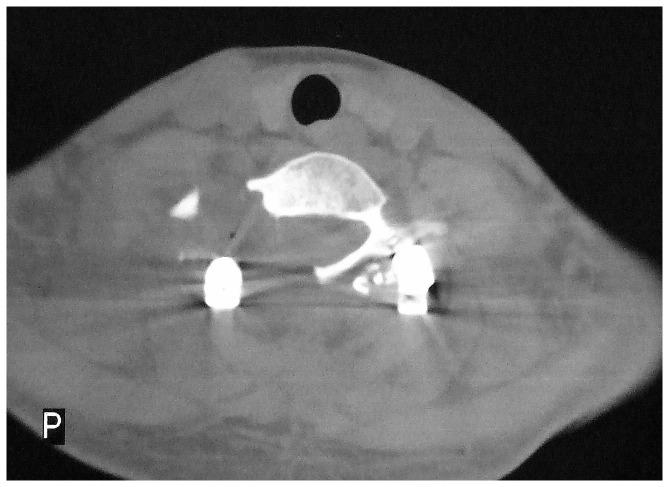

From June 2006 to July 2011, 18 patients with spinal osteoblastoma treated surgically were analyzed retrospectively. There were 11 males and 7 females with an average age of 27.5 years(range, 16-38 years). The tumors were located at C5 in 7, C6 in 6, C7 in 3, C6-T1 1 in 1 and T11 in 1. Based on WBB classification, 16 were 1-3 or 10-12 and 2 were 4-9 and 1-3. 18 operations had been performed with en bloc resection. A posterior approach was used for 16 patients, and a combined posterior and anterior approach was used for 2 patients. Reconstruction using instrumentation and fusion was performed using spinal instrumentation in 13 patients. We used visual analogue scales (VAS) to evaluate the change of pain before and after the operation, and the McCormick System to assess functional status of the spine. Imaging test was used to review the stability and recurrence rate of spine cord, and the confluence of graft bones.

All cases were followed up for 24-80 months (average, 38.4 months). The average surgical time was 120.8 minutes (range, 80-220 minutes), with the average intraoperative blood loss of 520 ml (range, 300-1200 ml). During the follow-up period, the VAS grade reduced from 6.46±1.32 to 2.26±1.05 (P <0.05). 15 patients had neurological function improved and 3 remained no change which was evaluated by McCormick scale for spinal function status at final follow-up.

Spinal osteoblastoma has its own specific radiographic features. There is some recurrence in simple curettage of tumor lesion. The thoroughly en bloc resection of tumor or spondylectomy, bone fusion and strong in Ter fixation are the key points for successful surgical treatment.